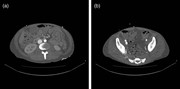

Abdominal pain and hematuria: duodenal perforation from ingested foreign body causing ureteral obstruction and hydronephrosis

Nina Kolbe and others

Journal of Surgical Case Reports, Volume 2016, Issue 2, February 2016, rjw018, https://doi.org/10.1093/jscr/rjw018